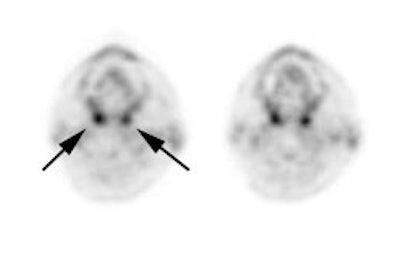

The tonsils are constantly exposed to antigens causing carious

degrees of physiologic inflammation [220]. Low to moderate FDG

uptake occurs in the lingual and palatine tonsils and at the base

of the tongue because of physiologic activity associated with the

lymphatic tissue in Waldeyer's ring [41]. However, tonsil uptake

can be high (SUV 3.11 (lingual) to 3.48 (palatine)) [103],

however, physiologic uptake is typically symmetric and asymmetric

uptake should be regarded as suspicious for malignancy [220].

There is usually uptake in the lymphoid tissue of Waldeyer's ring

[4]. The soft palate can also show tracer uptake [103]. Variable,

but typically low, uptake can be seen in the salivary glands which

secrete low amounts of glucose [41]. The parotids glands also show

mild, symmetric tracer uptake. Due to this physiologic activity,

low grade malignant lesions in the salivary and parotid glands may

be obscured [157]. Additionally, PET imaging is not able to

accurately differentiate benign from malignant parotid lesions as

benign tumors such as pleomorphic adenoma, oncocytoma, and Warthin

tumor are known to be FDG avid [312].

|

Head and neck activity: The images below show typical uptake in the tonsils (black arrows), submandibular glands (blue arrows), and parotid glands (red arrows) |